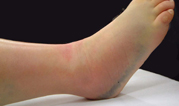

初診時の写真・X線

スライドの写真は初診時の外観で内出血の様子